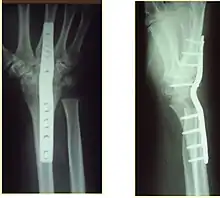

Surgery is generally indicated for displaced or unstable fractures.[18] The techniques of surgical management include open reduction internal fixation (ORIF), external fixation, percutaneous pinning, or some combination of the above. The choice of operative treatment is often determined by the type of fracture, which can be categorized broadly into three groups: partial articular fractures, displaced articular fractures, and metaphyseal unstable extra- or minimal articular fractures.[5]

Significant advances have been made in ORIF treatments. Two newer treatments are fragment-specific fixation and fixed-angle volar plating. These attempt fixation rigid enough to allow almost immediate mobility, in an effort to minimize stiffness and improve ultimate function; no improved final outcome from early mobilization (prior to 6 weeks after surgical fixation) has been shown. Although restoration of radiocarpal alignment is thought to be of obvious importance, the exact amount of angulation, shortening, intra-articular gap/step which impact final function are not exactly known. The alignment of the DRUJ is also important, as this can be a source of a pain and loss of rotation after final healing and maximum recovery.

If the fractures are unlikely to be reduced by closed means, open reduction with internal plate fixation is preferred.[5] Although major complications (i.e. tendon injury, fracture collapse, or malunion) result in higher reoperation rates (36.5%) compared to external fixation (6%), ORIF is preferred, as this provides better stability and restoration of the volar tilt.[5][23] Following the operation, a removable splint is placed for 2 weeks, during which time patients should mobilize the wrist as tolerated.[5]